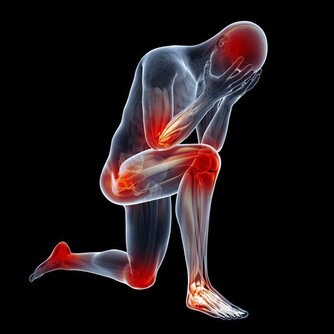

有文獻報導認為,癌細胞在增生分化過程中,會引起生長激素分泌異常。

大量的生長激素會刺激骨關節異常增生,侵犯膝、踝、腕等大關節,出現腫脹、疼痛等症狀。

據報導,老年人肺癌合併關節痛的發生率約佔10%至20%。

因此,對中、老年人突然逐漸加重的肩臂痛,無論是否伴有呼吸道症狀,

且肩臂痛經牽引或止痛藥治療,只能暫時緩解症狀而不能阻止疼痛進行性加重時,就需高度警惕。